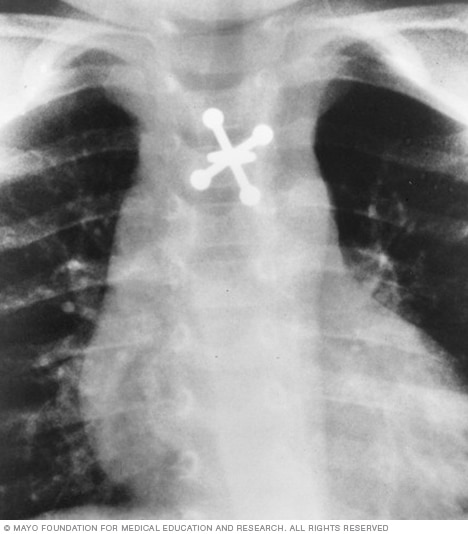

X-ray of swallowed jack

X-rays can locate metal objects your child has swallowed, such as this jack.

- Swallowed items. If a child has swallowed something such as a key or a coin, an X-ray can show the location of that object.